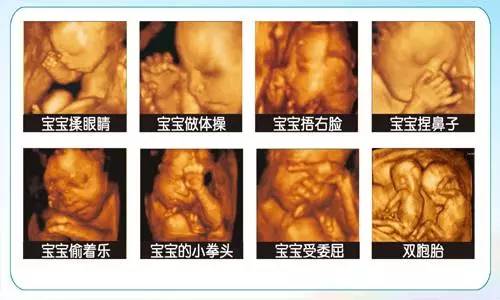

5D彩超是目前先进的高端超声影像设备,该技术具有更高的清晰度及分辨率。能360°立体精准的筛查胎儿面部、神经系统、消化系统、泌尿系统、骨骼、四肢、心脏疾病、大脑、超微血流、小器官等宫内发育情况,自动测量胎儿生产发育指标,是应用于胎儿产前排畸、缺陷儿终极诊断及完整记录胎儿宫内高清动态的尖端设备。

1、5D彩超就是采用4D超声图像加上空间维度参数,获取更加立体、逼真的四维图像,超越了传统灰阶超声的大部分限制。相比四维彩超,5D彩超在排畸功能上更完善、观察范围更广、画面更清晰,胎儿排畸准确率和分辨率更高。

2、五维(5D)比四维彩超更直观、清晰,并且可以把宝宝在宫内的一举一动实时记录成视频,通过显示器呈现,实时观享,打造宝宝世界里的第一部“电影”。

孕22~26周系统排畸:这段时期胎儿大小及羊水适中,局部结构和运动状态比较清晰,体表也比较丰满,有利于胎儿5D超声成像和胎儿畸形筛查,是排畸的适宜时期。